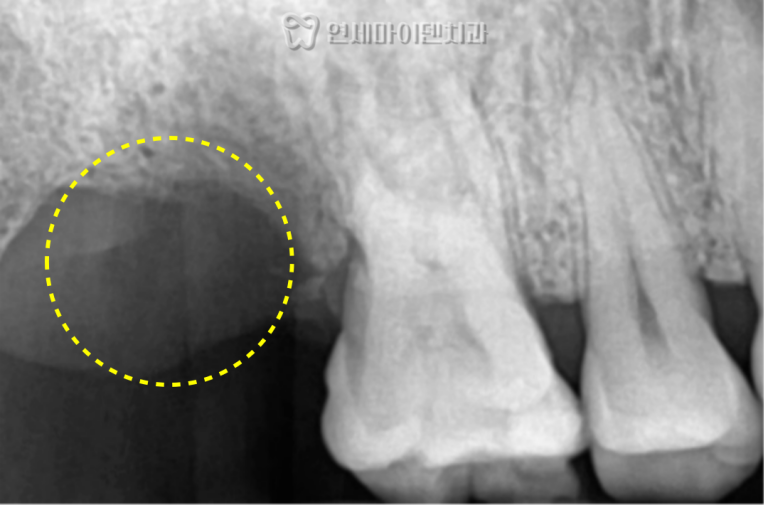

CT 촬영 결과, 치아 후방부의 뼈는 완전히 흡수되어 있었지만

전방부에는 일부 치조골이 남아 있어서

고정력을 확보할 수 있었습니다.

발치 직후 치근 표면을 관찰한 결과,

세균막이 치근 전체를 덮고 있어 뼈 재생이 불가능한 상태였습니다.

좌측 하악 제2대구치 역시

심한 치조골 흡수가 관찰되었습니다.